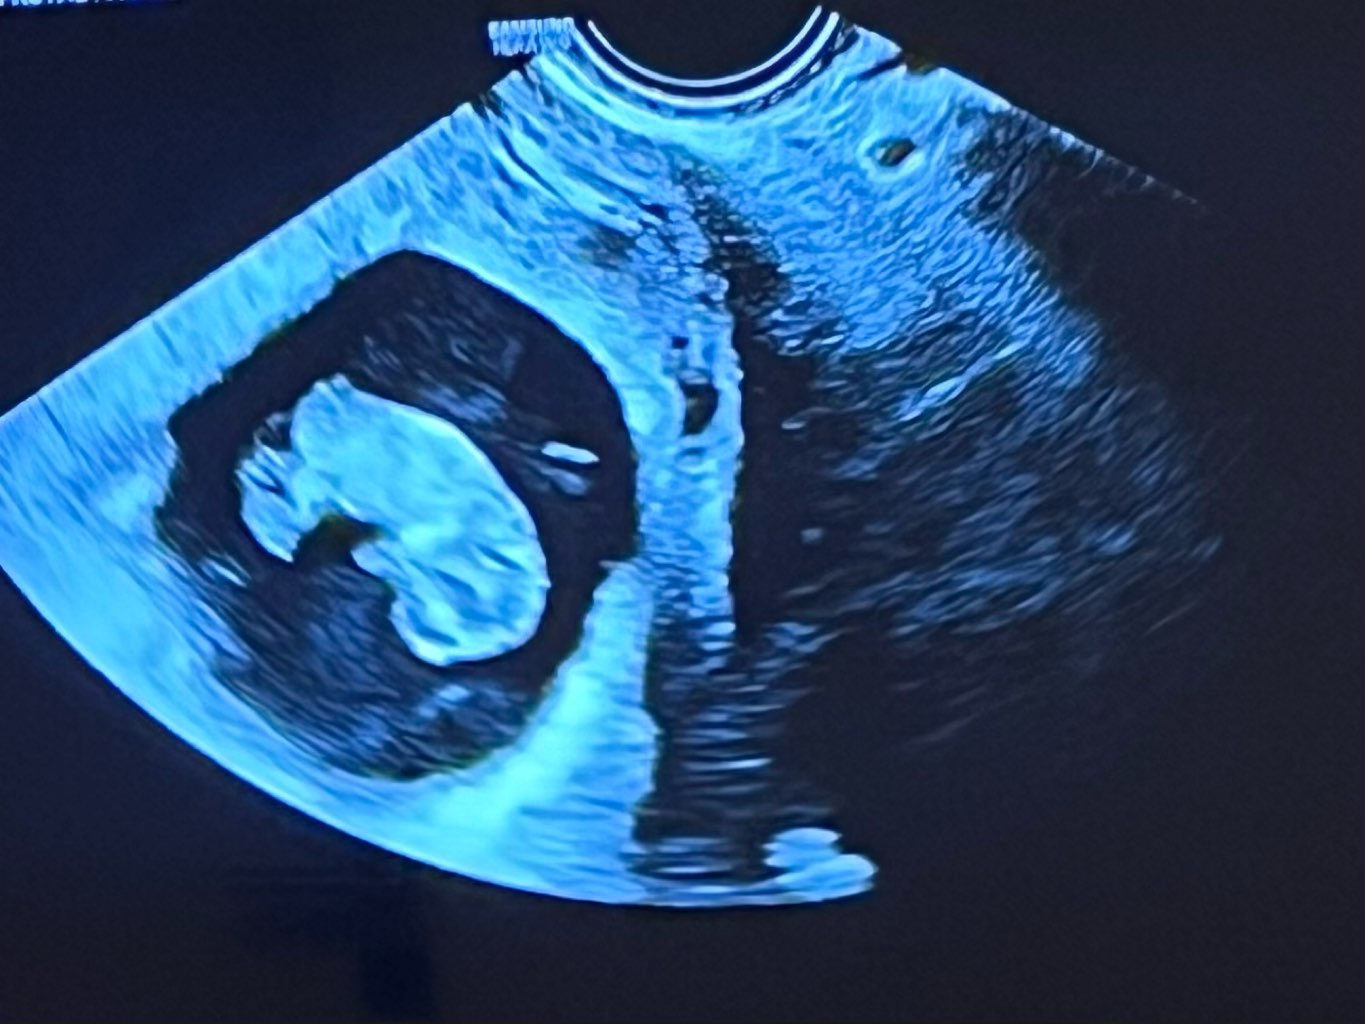

Melduję się że słyszałam dzisiaj jak bobasowi bije ❤️. Ciąża wychodzi o 4 dni młodsza bo wg USG 9+3 a z OM 10+0. Uspokoiłam się. Mam kartę ciąży oraz skierowanie na prenatalne, jutro będę się umawiać.